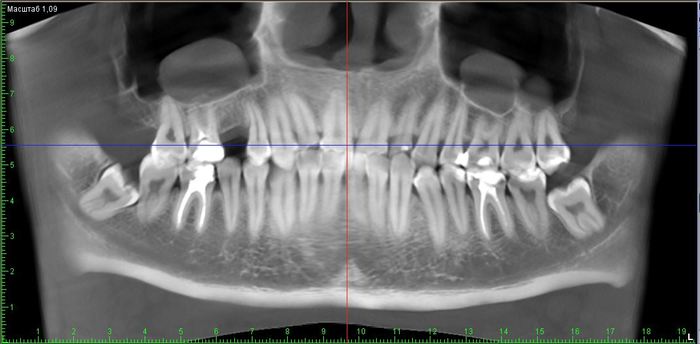

Необходима консультация по поводу удаления зубов мудрости (2 нижние восьмерки).

До этого ходил в 2 платные клиники на консультацию и в 1 поликлинику (бесплатную).

В 1 платной врач сказал "конечно удалять" и озвучил стоимость 6.500 за 1 зуб.

В другой платной врач сказал можно и не удалять, но один который подпирает лучше удалить - стоимость 8 тыс с ультазвуком.

В бесплатной государственной поликлинике врач сказал не надо удалять - они лежат в кости и уже выросли, ничего не будет.

Теперь вопрос - что делать с зубами удалять или оставить?

Снимок томографии ниже.